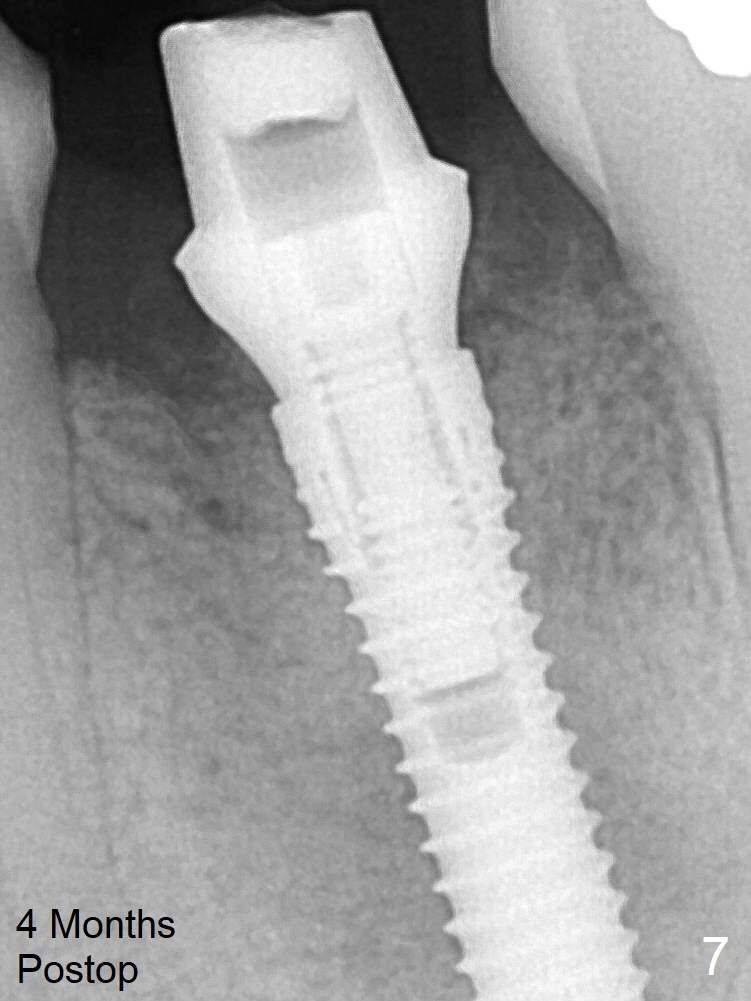

It appears that a 3.8x18 mm implant is not placed deep enough. Following 3-4 more turns of the implant and placement of a 5.5x4(3) mm abutment (Fig.5 A), allograft is placed (*). The bone around the implant appears to have regenerated 4 months postop (Fig.7).